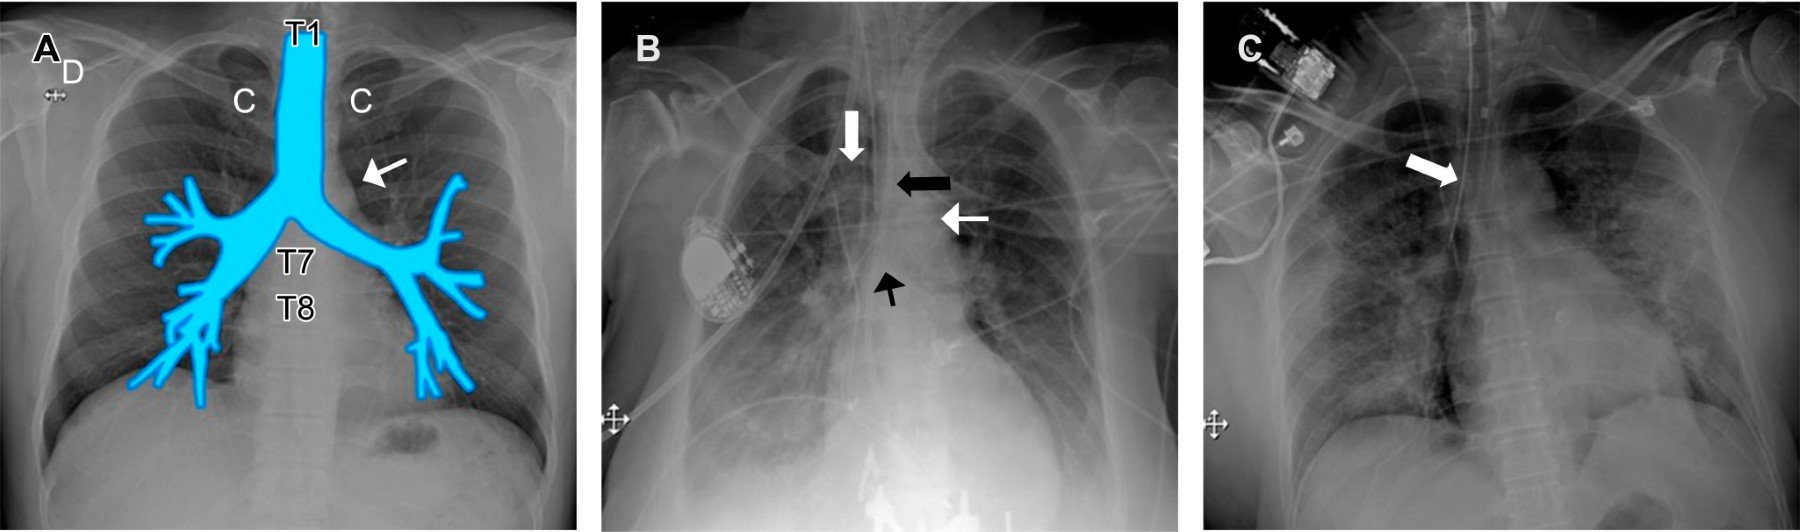

En cuanto a la anatomía, destacamos que la pared posterior de la tráquea es membranosa predisponiéndola al trauma, cuando la lesión se asocia al dispositivo endotraqueal el sitio de lesión más común es éste. Los hallazgos radiológicos incluyen neumotórax bilateral, enfisema subcutáneo masivo (si la lesión involucra la hipofaringe el aire se extiende y diseca la región cervical)1 y neumomediastino (Figura 2).8,14,15

Existen algunas imágenes en relación al dispositivo que nos permiten sospechar una ruptura traqueobronquial como la disposición oblicua del tubo con desviación hacia la derecha, y sobredistensión del globo con un diámetro anteroposterior mayor de 2.5 cm.8,15

Cuando el defecto es significativo y coincide con el nivel de la laceración, el globo mostrará herniación adquiriendo una configuración "en reloj de arena" (ocasionalmente se presenta como complicación de la traqueostomía);14 esto se puede identificar en la tomografía computarizada hasta en 70 y 100% de los casos.16